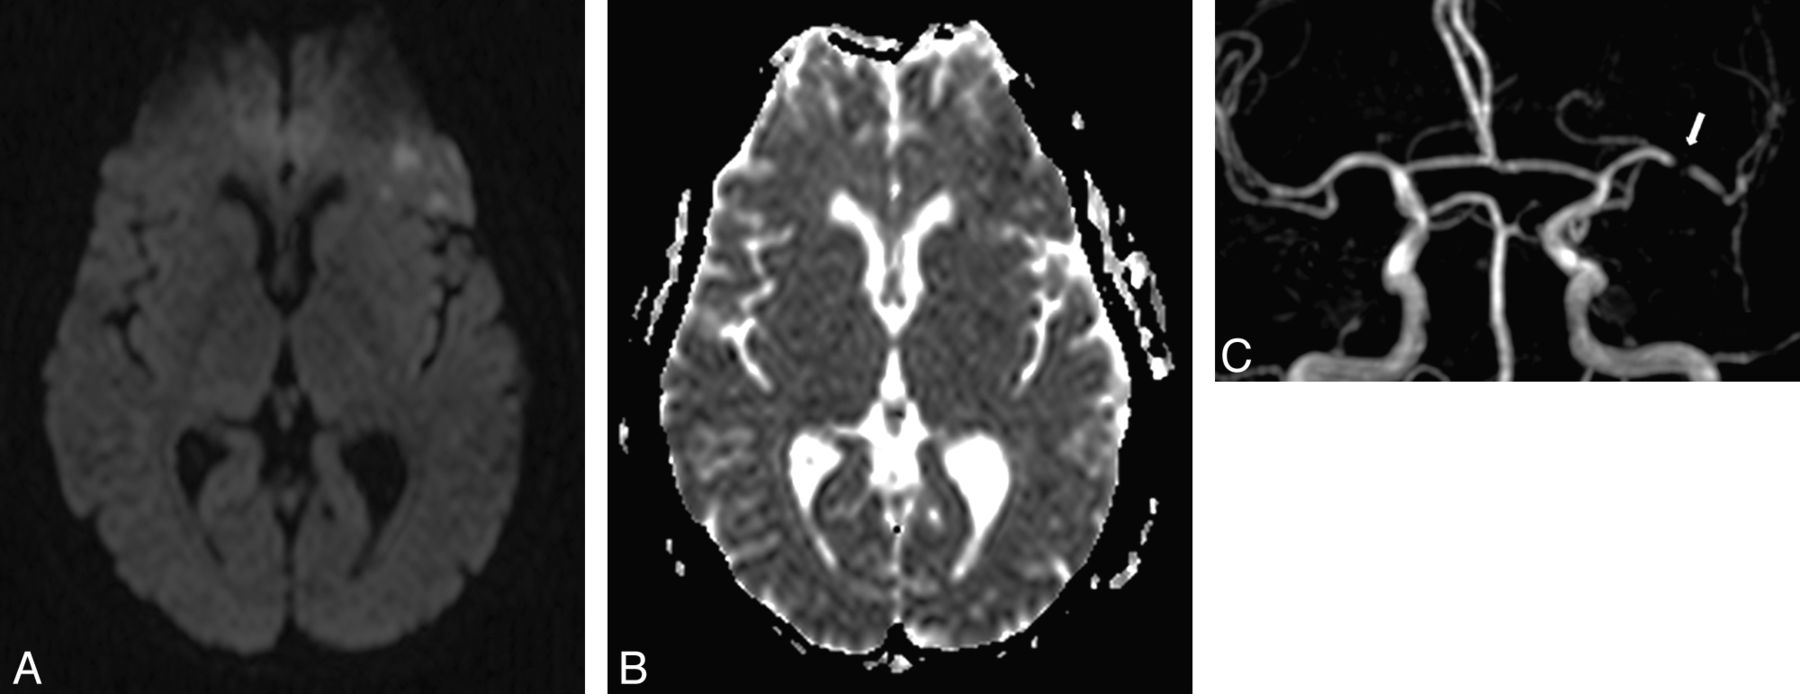

A 57-year-old woman with right transient hemiparesis (clinical duration = 2 minutes, delay since the first clinical symptom = 12 hours). ABCD2 score = 4. A, DWI shows some foci of high signal intensity in the left frontal lobe with a decrease of ADC on the ADC map (B). C, 3D TOF reveals a significant proximal stenosis of the left M1 segment (arrow). The patient had another right transient impairment in the subsequent 48 hours.